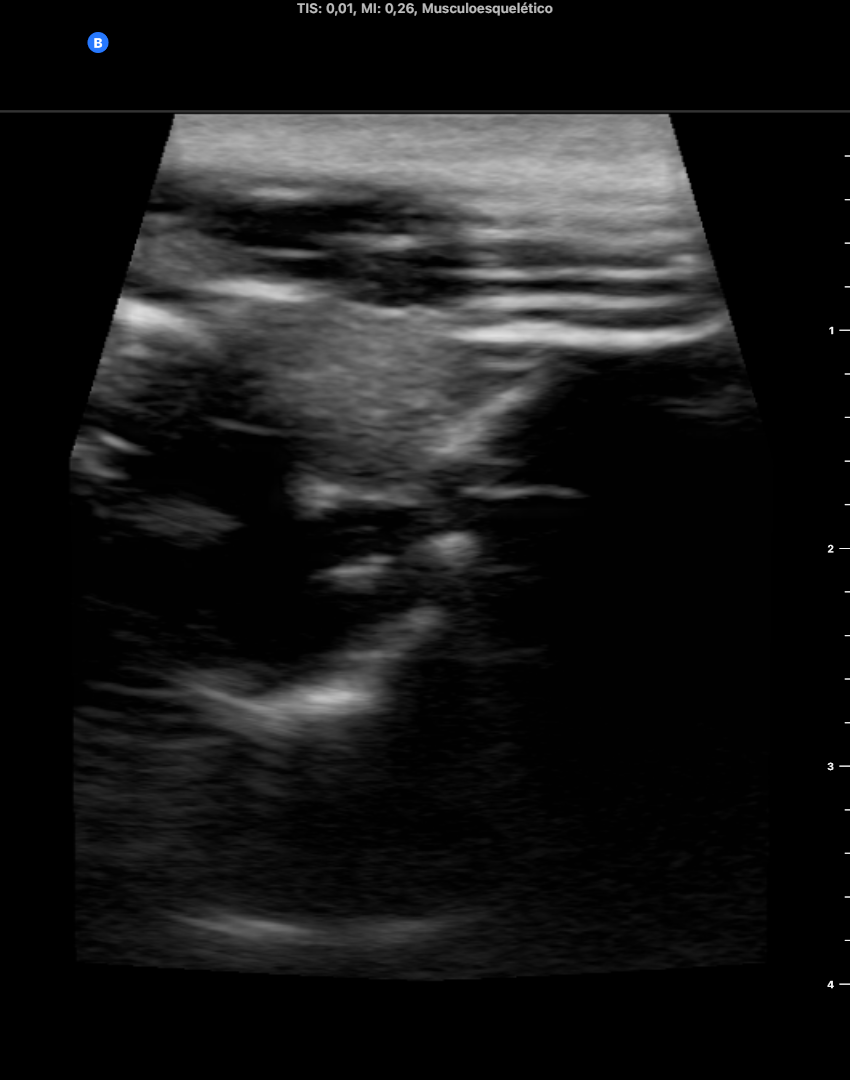

Ecoscopia: líneas A artefactuales a nivel de zona cervical izda. que borra la anatomina del tiroides y vasos cervicales. Anatomía cervical derecha normal. Ventana pulmonar sin neumotórax en modo M. Ventana cardíaca en eje paraesternal corto borrado por líneas A que no permiten valoracion correcta. Abdomen sin líquido libre ni líneas A.

Ecoscopia tras 1 semana del diagnóstico ecoscópico normal a todos los niveles anatomicos (cervical, pulmonar, cardíaco, abdominal).